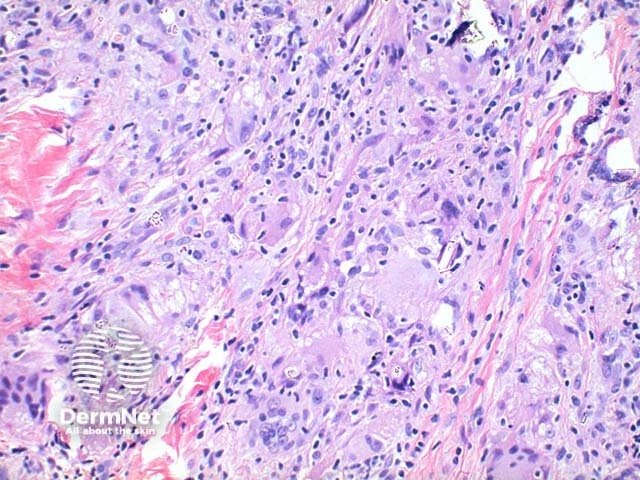

Scanning power view of sarcoidosis shows a granulomatous reaction pattern (Figure 1) characterised by multiple discrete predominantly epithelioid granulomas (Figures 2 and 3). Necrosis is uncommonly seen. The granulomas are typically ‘naked’ with few surrounding lymphocytes and a rim of mild dermal fibrosis.

Asteroid bodies are star shaped cytoplasmic inclusions. Schaumann (conchoidal) bodies are concentrically lamellated calcified nodules seen within the cytoplasm of multinucleated cells. While frequently seen, these findings are not specific to sarcoidosis.

Foreign bodies are not uncommonly seen within sarcoidal granulomas (Figures 2, 3 and 4) and are more common within sites prone to trauma. The presence of birefringent material therefore does not exclude sarcoidosis. Foreign material may serve as a nidus for sarcoidal granuloma formation in some cases.

Figure 3